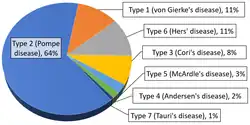

Epidemiology

Overall, according to a study in British Columbia, approximately 2.3 children per 100,000 births (1 in 43,000) have some form of glycogen storage disease.[103] In the United States, they are estimated to occur in 1 per 20,000–25,000 births.[10] Dutch incidence rate is estimated to be 1 per 40,000 births. While a Mexican incidence showed 6.78:1000 male newborns.[12][104]

Within the category of muscle glycogenoses (muscle GSDs), McArdle disease (GSD-V) is by far the most commonly diagnosed.[59]